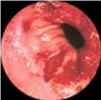

שיטת האבחנה העיקרית היא הגסטרוסקופיה המאפשרת לראות היטב את הכיב ומיקומו, ואת השינויים ברקמה שסביב לכיב. הדיוק האבחנתי של הגסטרוסקופיה הוא 95%. הגסטרוסקופיה מאפשרת לאבחן את מקור הדימומים הפעילים (תצלומים 3.3) וכן ליטול ביופסיות מממצאים חשודים ולקבל אבחנה היסטולוגית. הגסטרוסקופיה חשובה לאבחנה מבדלת בין דימום שמקורו בדליות הוושט (תמונה 4.3) לבין דימום שמקורו בקיבה או בתריסריון. כיב חוזר בקו ההשקה, קרעים ברירית (בתסמונת על-שם מלורי-וייס (Mallory-Weiss)) (תמונה 5.3), דלקת קיבה וארוזיות ניתנים לאבחנה ולהוכחה, בעיקר בעזרת הגסטרוסקופיה, ואין אפשרות להדגימם כראוי ברנטגן (תמונה 2.3 , 6.3).